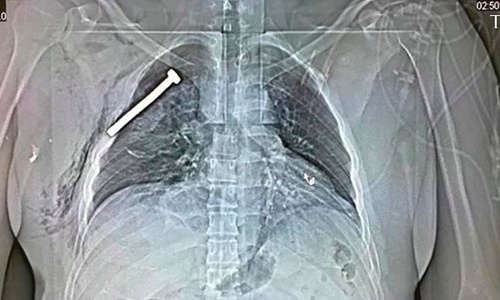

Ảnh chụp X-quang của một nạn nhân cho thấy một chiếc đinh lớn nằm trong lồng ngực người này

IS tuyên bố những kẻ tấn công đã cho kích hoạt đai bom gây ra các vụ nổ. Tuy nhiên, theo các nhà điều tra, đai bom không thể có sức công phá lớn đến thế.Theo một quan chức y tế Brussels, các quả bom còn nhồi đầy đinh. Đây là cách mà những kẻ chế tạo bom thường dùng để gia tăng tối đa mức độ sát thương.

"Bom chứa đinh sẽ tạo ra nhiều thương vong hơn. Một số nạn nhân đã bị đinh găm sâu vào cơ thể", Marc Decramer, người phát ngôn Bệnh viện Đại học Gasthuisberg ở Leuven, nói. Ảnh chụp X-quang của một nạn nhân cũng cho thấy một chiếc đinh lớn nằm trong lồng ngực người này.